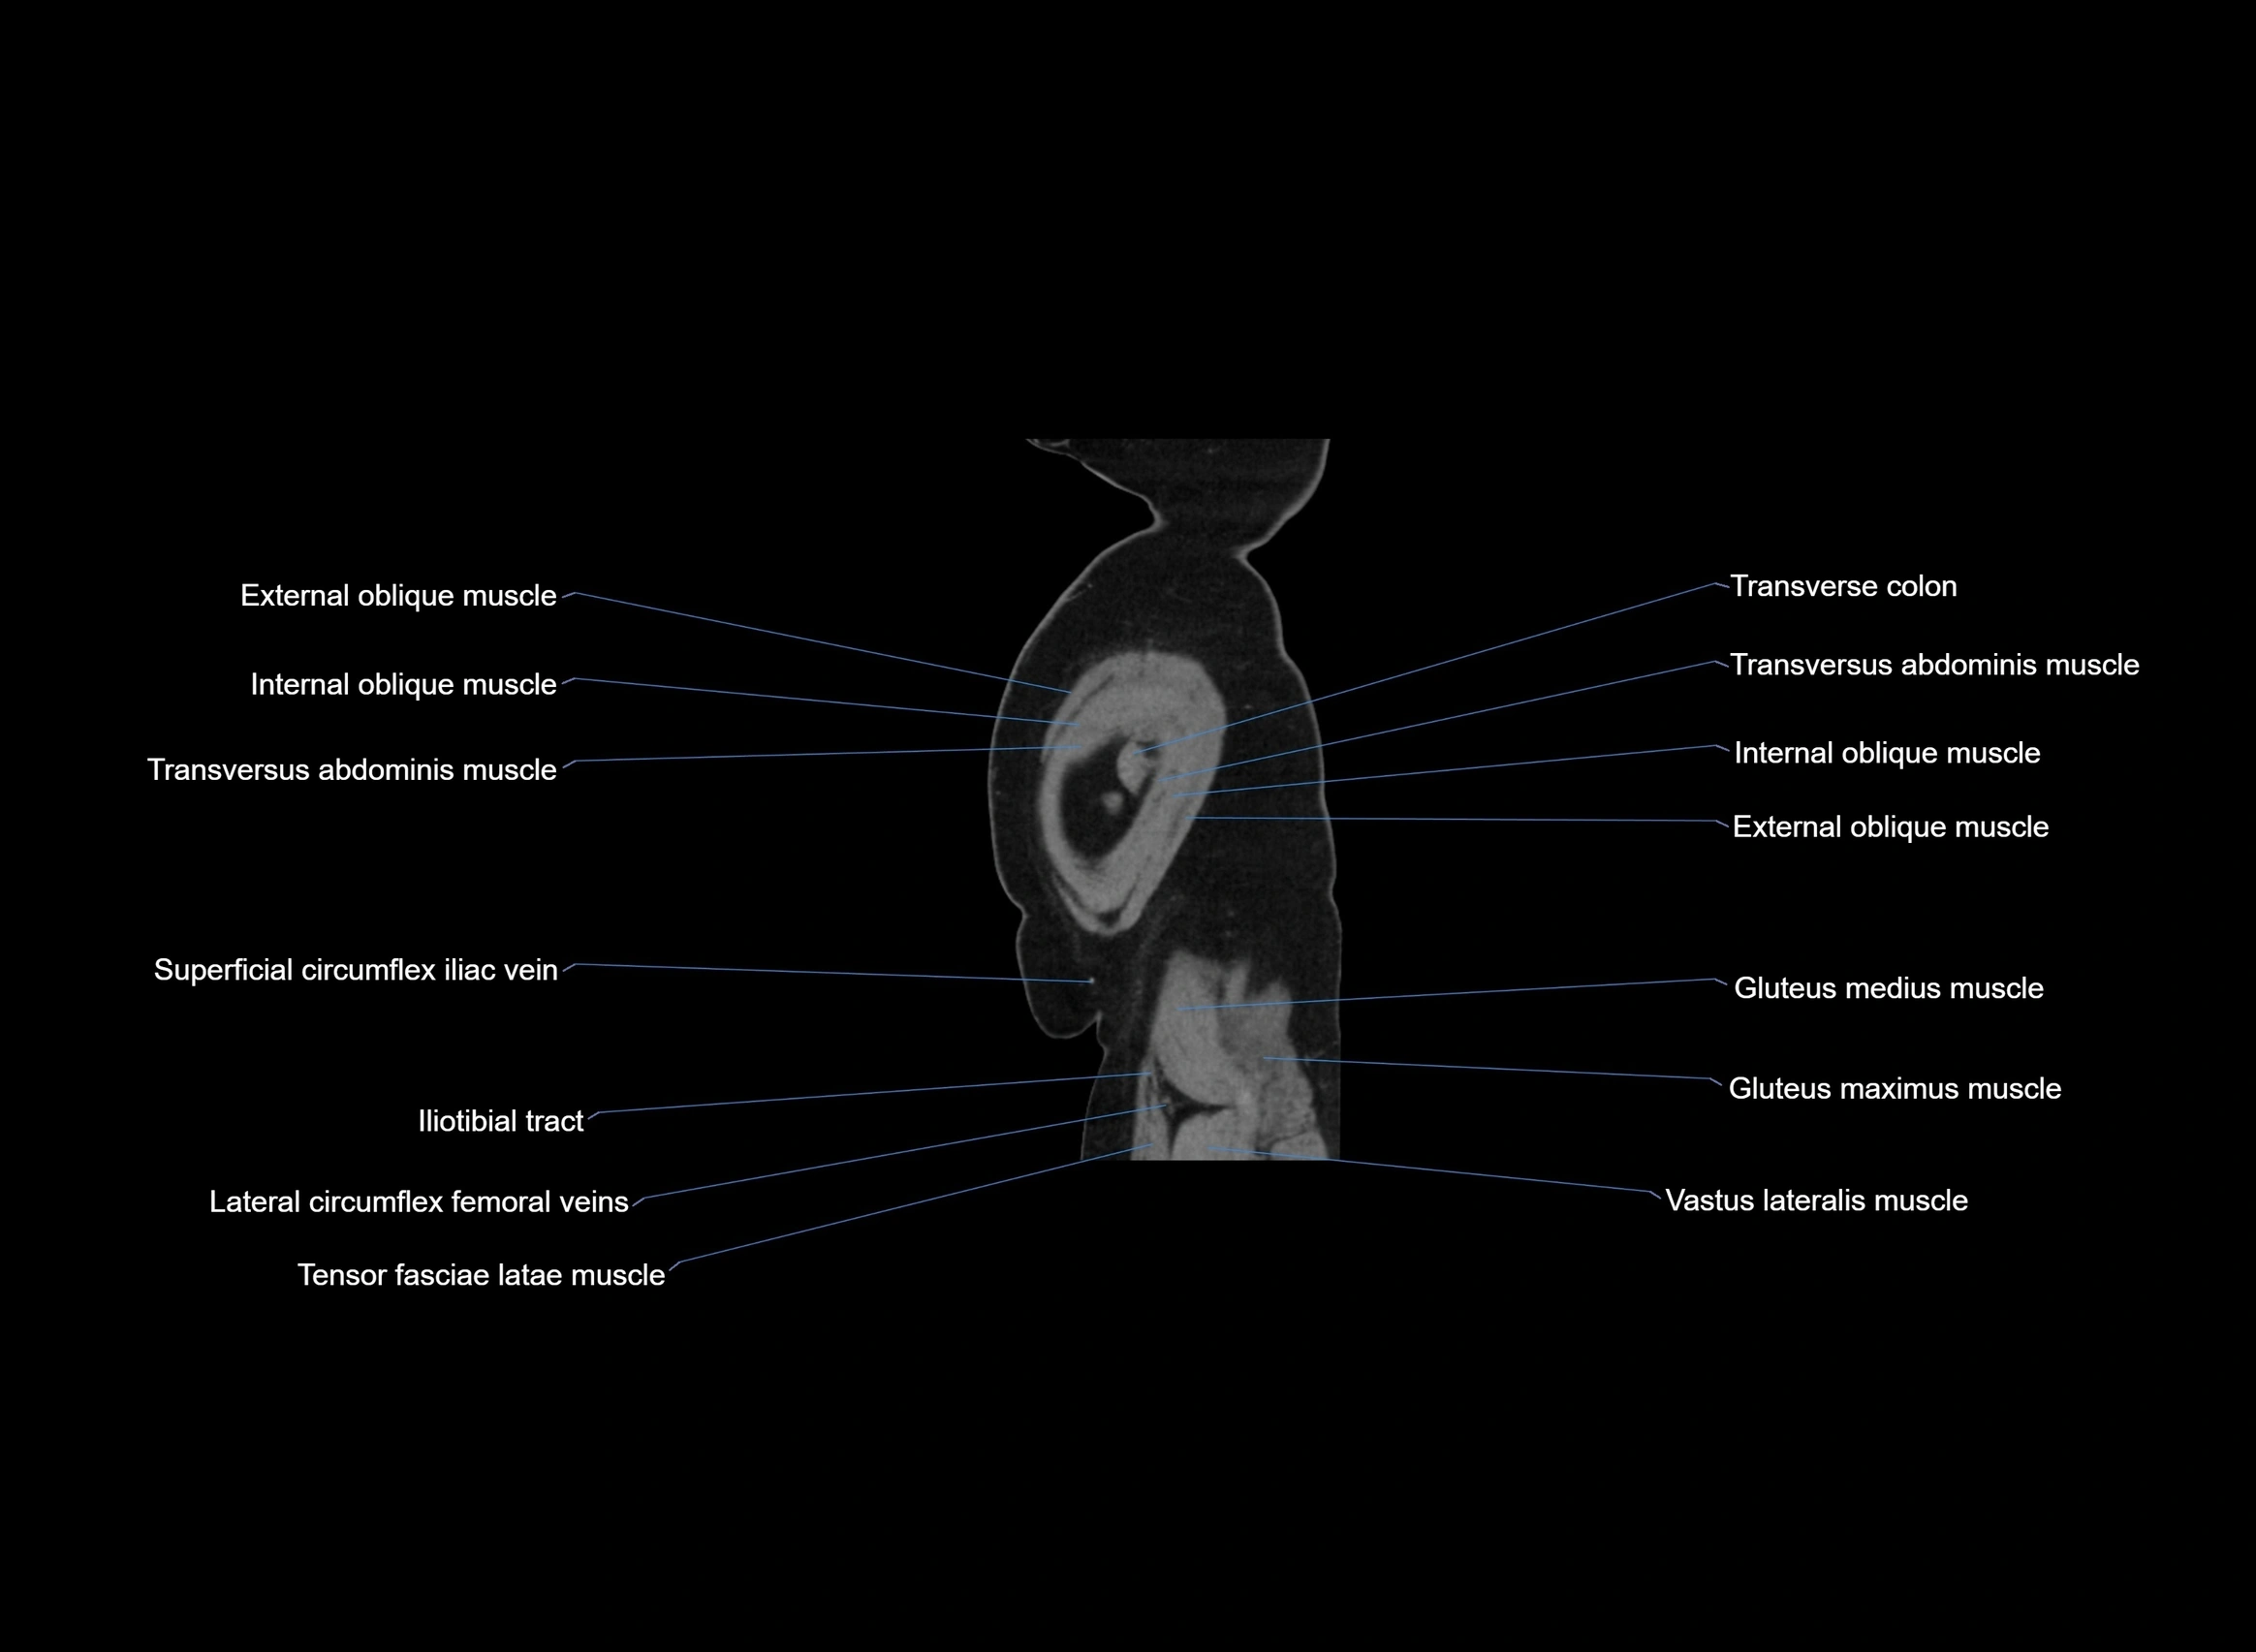

CT images